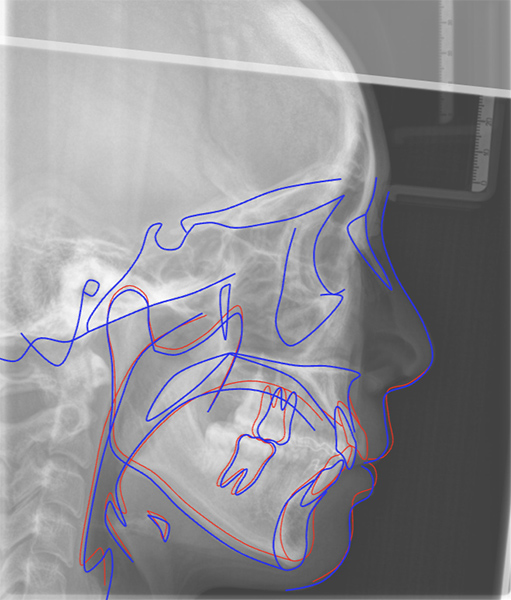

セファログラムをアップロードするだけで、AIが顔貌・骨格・咬合・軟組織・気道まで、159測定点をわずか数秒で自動トレース。従来30分以上必要だった作業を劇的に効率化します。 また専門医レベルの精度で、経験や習熟度に左右されない標準化が可能です。 手動修正にも対応し、効率と精度の両立を実現します。 DIP Magic Compare™

治療の変化を一目で可視化

治療前後のセファログラムをAIが自動で重ね合わせ。骨格や歯の変化を視覚的に確認し、治療状況を正確にモニタリングできます。

患者様に対する説明資料としての活用で、治療計画への理解と納得を深めます。